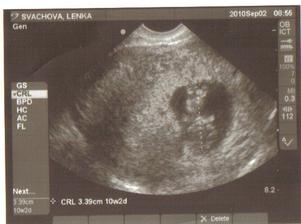

2.září: další kontrola, sestřička si zahrála na upíra a vzala mi 5 ampulek krve, dnešní UTZ parádní, prcek sebou mrskal jako o život a bude asi i fotogenickej, fotka z UTZ je úžasná, na kontrole za 14 dní už dostanu průkazku